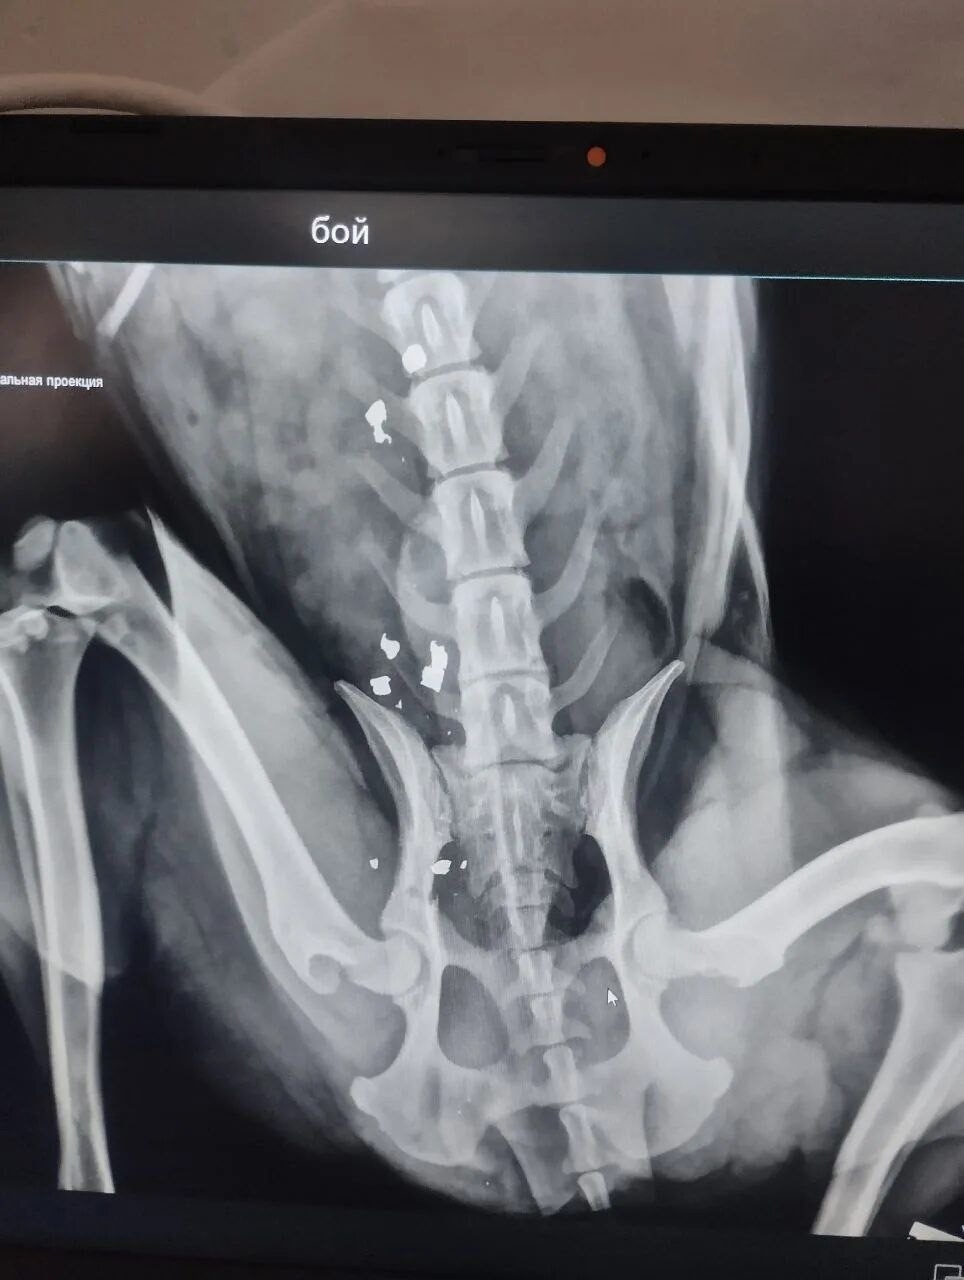

Когда-то Боя уже возили в Волгоград на рентген, но полноценного лечения он не получил и снова оказался на улице. Итог — инвалидность и гниющая заживо конечность.